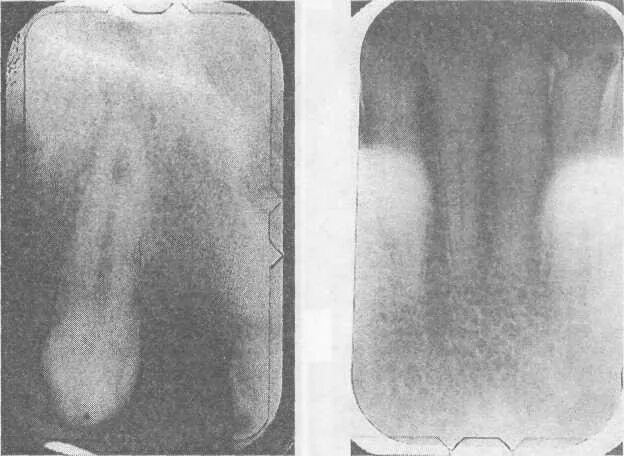

Признаки резорбции